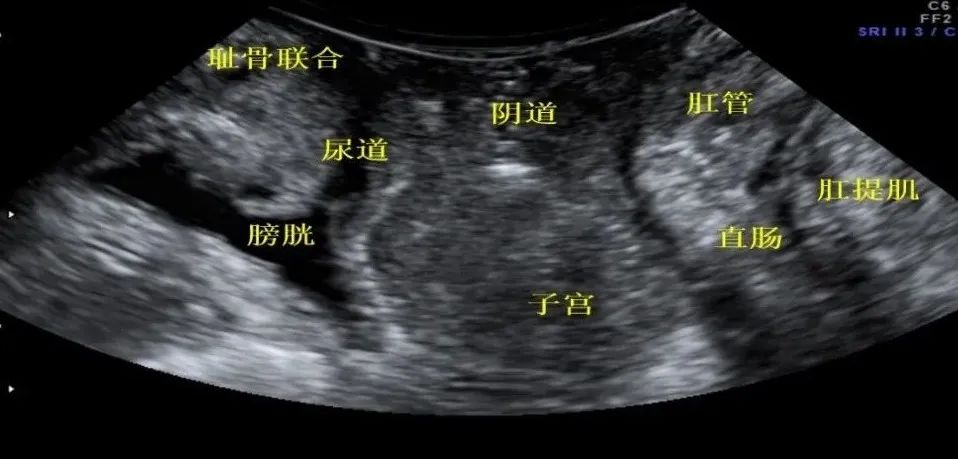

盆底三维超声是检查盆腔脏器是否有损伤而导致位置下降,比如膀胱、直肠,子宫是否因分娩等因素在用力向下排便时,从正常位置向下偏移,所以女性做盆底功能检查有效评估上述器官的功能情况,是非常必要的,特别是产后女性更应及时检查盆底功能,并及时进行盆底功能训练。

女性正常盆底结构的超声表现